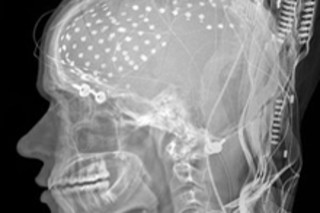

A curious experiment has given scientists an unprecedented look into the human brain as it goes about a vital and everyday task: processing and speaking words. The study, published in Science, found that the brain carries out three steps of the task in about half a second, and that all the activity happens sequentially in the same small brain region, known as Broca's area. The researchers took advantage of a rare procedure

in which epilepsy patients allow doctors to implant dozens of electrodes directly into their brains. While they are awake, the patients answer questions so that doctors can determine which parts of the brain are necessary to maintain language and which parts can be safely removed to treat epileptic seizures [Los Angeles Times].

Three such patients agreed to take part in the language experiment, were given long lists of verbs, and were asked to change some of them to the past or present tense before saying them out loud. The electrodes picked up regular pulses of activity in the brain region

called Broca's area, which lies beneath the left temple. The area of the brain is named after a 19th century physician named Pierre Paul Broca, who became famous for his study of two patients who couldn't speak [NPR News].